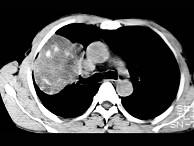

根据所提供的图像,选择最可能的诊断 ( )A、机化性肺炎B、局限性不张C、胸膜间皮瘤D、球形肺炎E、肺内软骨肉瘤

问题 根据所提供的图像,选择最可能的诊断 ( )

选项 A、机化性肺炎 B、局限性不张 C、胸膜间皮瘤 D、球形肺炎 E、肺内软骨肉瘤

答案 E